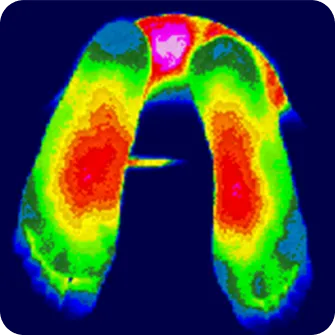

몸에서 발생하는 열에너지를 감지하여 눈에 보이지 않는 통증 부위와

신경이 손상된 부위를 찾아내고 진단하는 검사

뇌의 스트레스와 자율신경 실조에 따른 교감신경 항진에 의한

근육 긴장 및 통증 증가 패턴 파악